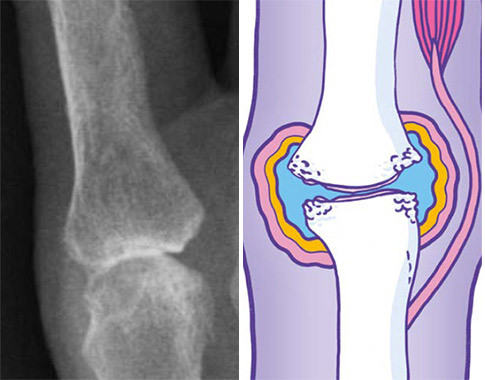

The structures that are shown below represent diagrammatically the changes that occur in the two main types of arthritis. However, it is important to identify those cases where pain may appear to arise from the joint but is in fact referred pain – for example, where the patient describes pain in the left shoulder, which might in fact be referred pain from the diaphragm, the neck, or perhaps ischaemic cardiac pain. In cases where examination reveals no abnormalities in the joint, other clues will be obtained by taking a thorough history. A common cause of widespread pain with normal joint examination for example is fibromyalgia.

X-ray and diagrammatic representation of an index finger MCP joint affected by osteoarthritis